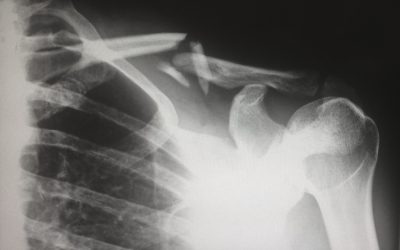

La osteoporosis es una enfermedad caracterizada por la pérdida de masa ósea y una mayor fragilidad de los huesos. Aunque es más común en mujeres posmenopáusicas, también puede afectar a hombres y personas jóvenes debido a factores como la falta de actividad física, deficiencias nutricionales y predisposición genética.

Los huesos, al igual que los músculos, responden al estrés físico. Cuando realizas ejercicios específicos que estimulan el sistema musculoesquelético, promueves la formación de nuevo tejido óseo y fortaleces los huesos existentes. Esto no solo ayuda a prevenir fracturas, sino que también mejora la postura, el equilibrio y la fuerza general.